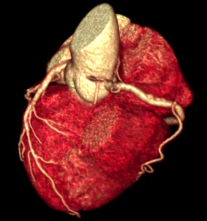

Công nghệ tim mạch Aheart

Phương pháp chỉnh sửa ECG

Khám phá nhiều hơn, đi sâu vào từng chi tiết

Hình ảnh lâm sàng